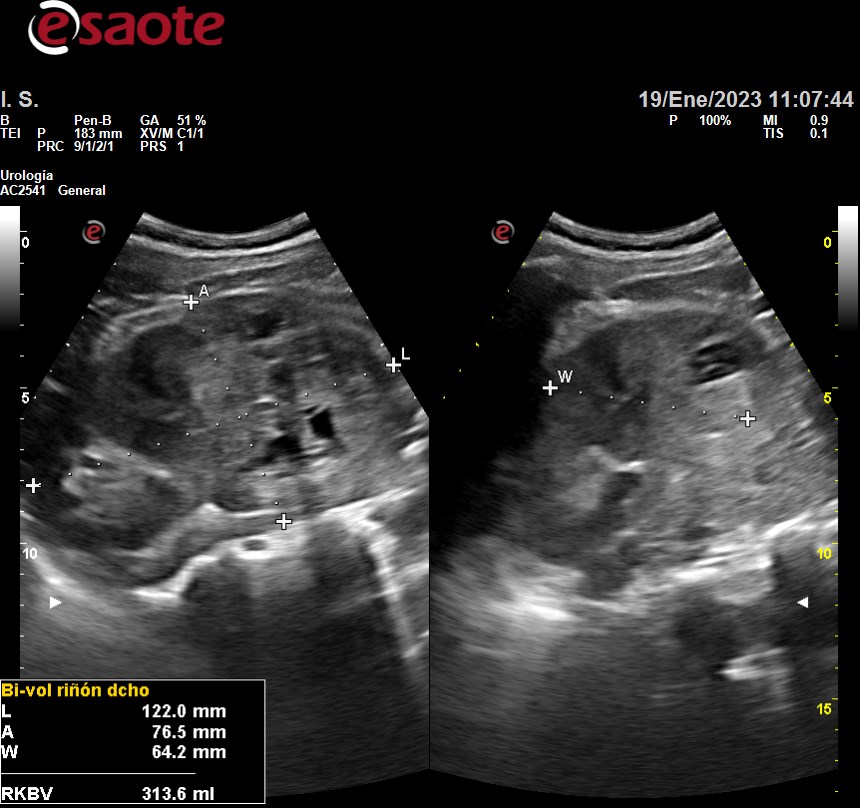

Hallazgos ecográficos

Siguiente hallazgo:

• Riñón derecho aumento tamaño 12.2 x 76.5 x 64.2, irregular, heteroecoico con presencia de áreas hipoecoicas sin litiasis ni dilatación sistema pielocalicial.

Ecografía hospital: tumoración renal derecha primaria, predominantemente sólida con zonas quísticas, en cortical externa interpolar - polar inferior, con proyección al seno renal, sin infiltración del pedículo vascular.